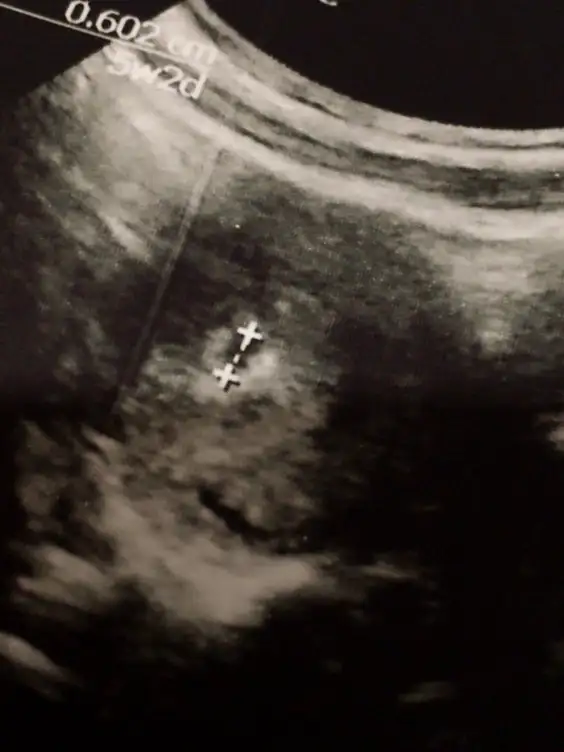

Merhaba hanımlar. Bugün başka bir Dr bulup gittim. Keseyi gördü gelişmemiş 10 gün önceki boyutta kalmış. Kürtaj yerine ilaç ile düşürme dedi yatış verdi. Yaşayan vsr mı çok ağrı olurmu çok korkuyorum 😑 5 haftalık İl kalmış öyle.

Eklentiler

• 3B914592-E810-494D-ABE4-B0B67BF5E476.webp

3B914592-E810-494D-ABE4-B0B67BF5E476.webp

13,7 KB · Görüntüleme: 61